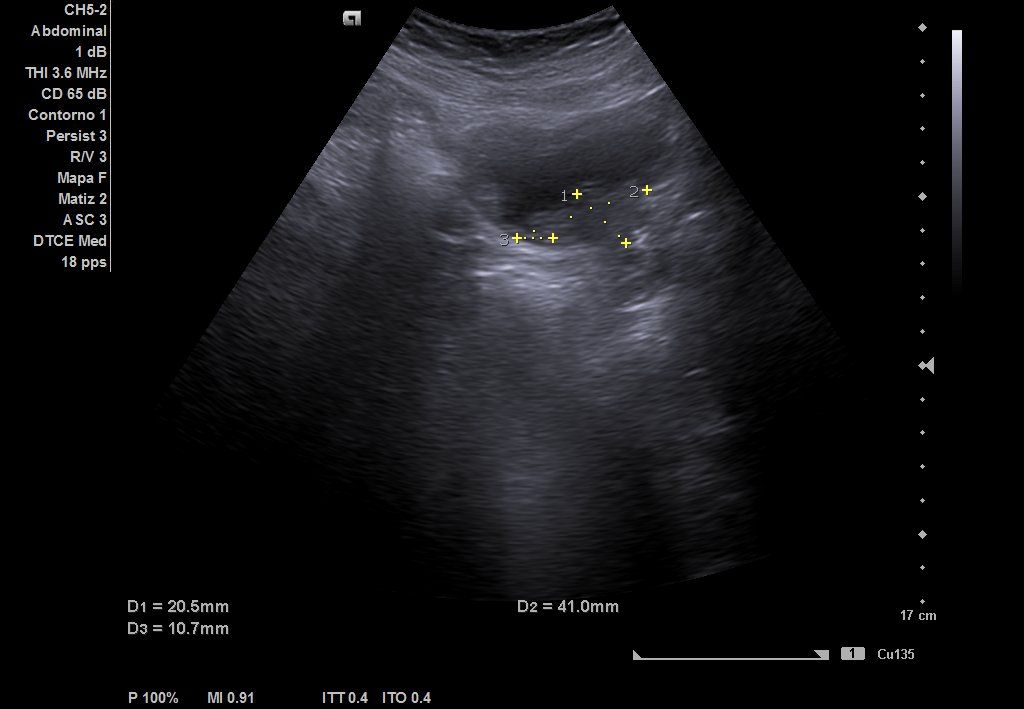

Descripción de los hallazgos ecográficos y las imágenes más relevantes para la resolución del caso

Ecografía urinaria: vejiga bien replecionada, observándose masa en trígono de 20 x 12 mm. Riñón derecho con dilatación pielocalicial moderada, sin hidronefrosis. Riñón izquierdo sin alteraciones reseñables.

Ecografía reglada: ureterohidronefrosis grado III secundaria a lesión en uréter medio-distal. Vejiga parcialmente replecionada con material ecogénico en suelo vesical con aparente doppler color e interior. Posible coágulo vs lesión subyacente.